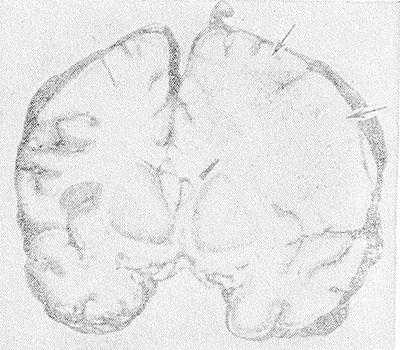

Рис. 1. Фронтальный срез головного мозга больного, умершего от геморрагического лейкоэнцефалита: белое вещество справа более отечное, усеяно мелкими петехиальными кровоизлияниями (указаны стрелками), прилежащие участки коры нечетко очерчены.

Макроскопическое исследование мозга при Л. выявляет расширение борозд и атрофию извилин. На срезе полушарий определяются различного размера участки деструкции и демиелинизации во всех отделах мозга, преимущественно в белом веществе, но захватывающие различные участки серого вещества коры (рис. 1). В наиболее пораженных отделах мозг имеет губчатую консистенцию, желудочки мозга умеренно расширены.